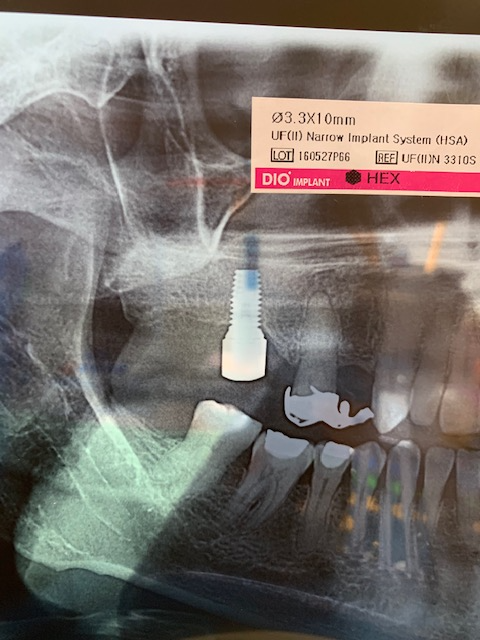

¿Podrían ayudarme a identificar el implante de la 36 ( mas mesial)?

Buenas tardes! Paciente que viene con corona floja, era cementada y um compañero intentando apretar el tornillo del pilar ( que se había aflojado) fresó la cabeza del tornillo. Necesito [...]